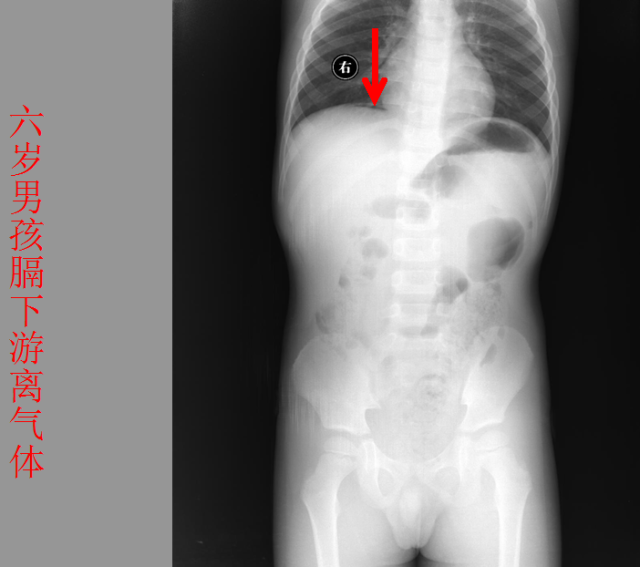

急腹症篇

05